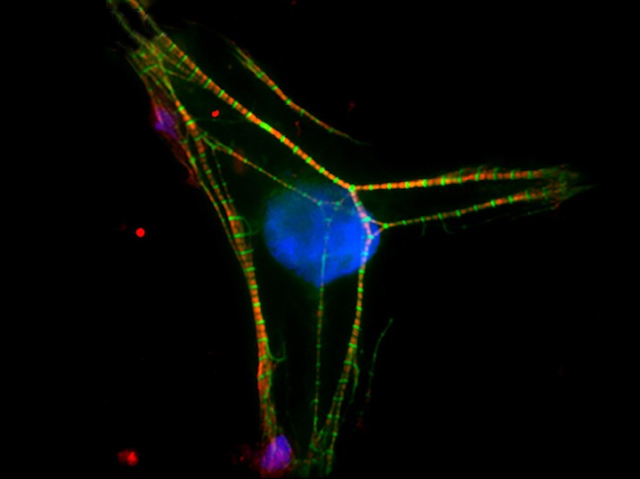

Mutations at Heart

Filamin C protein is key for maintaining the internal structure of both heart and skeletal muscle cells. This study reveals mutations in the filamin C gene and their molecular effects underlying cardiomyopathies